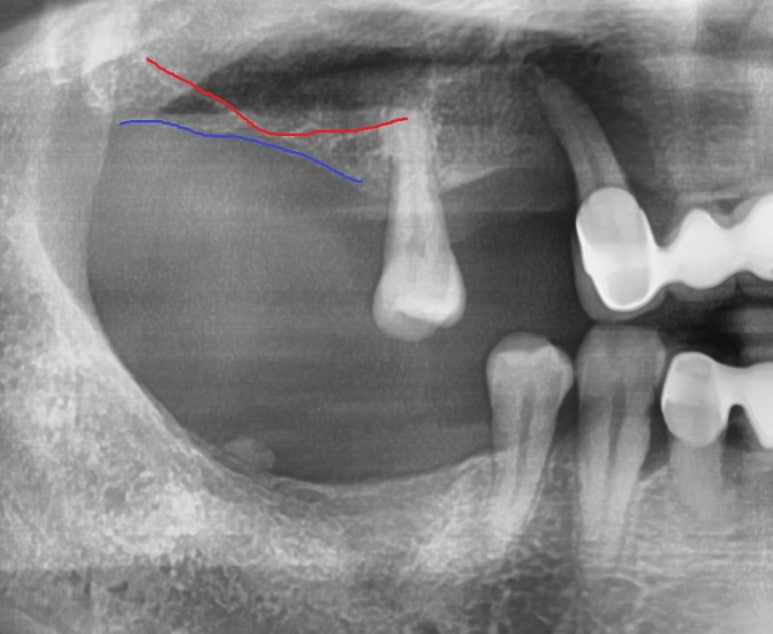

빨간선(상악동 하방), 파란선(치조골경계부위)

위의 엑스레이 사진에서 보듯이 상악동이라 불리는 공기주머니가 많이 내려와 있어서

그 부위에 어금니 임플란트를 심을 수 있는 뼈의 수직길이가 극히 적어서

일반 상악동 거상술보다 더 고난도의 상악동거상술 상악동 뼈이식까지 해야하는 상황이었습니다.

그리고 아래쪽에 어금니도 없는 부분도 어금니임플란트를 하기로 하였습니다.